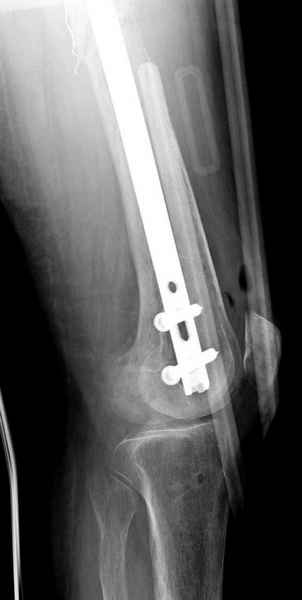

С минимальным рассверливанием и ретроградным методом провели остеосинтез бедра 12 мм гвоздем. (17-20)

Имя     : 17 ap final.jpg

Тип     : image/jpeg

Размер  : 16278 байтов

Описание: отсутствует

Url     : http://weborto.net:8080/pipermail/ortho/attachments/20090331/478d25c4/attachment-0026.jpg

Вложение не в текстовом формате было извлечено…

Имя     : 18 ap final distal.jpg

Размер  : 20954 байтов

Url     : http://weborto.net:8080/pipermail/ortho/attachments/20090331/478d25c4/attachment-0027.jpg

Имя     : 19 lat final.jpg

Размер  : 15552 байтов

Url     : http://weborto.net:8080/pipermail/ortho/attachments/20090331/478d25c4/attachment-0028.jpg

Имя     : 20 lat final distal.jpg

Размер  : 19582 байтов

Url     : http://weborto.net:8080/pipermail/ortho/attachments/20090331/478d25c4/attachment-0029.jpg